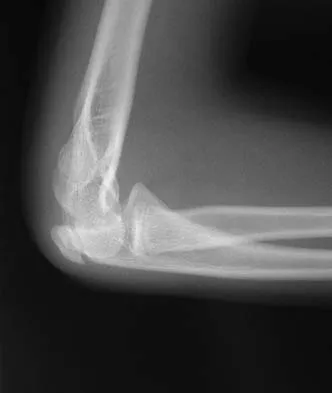

Figure 3 shows the radiographs of a 32-year-old man who fell 12 feet onto his outstretched arm and sustained a fracture-dislocation of the elbow. Initial management consisted of closed reduction of the dislocation. Surgical treatment should now include repair or reduction and fixation of the